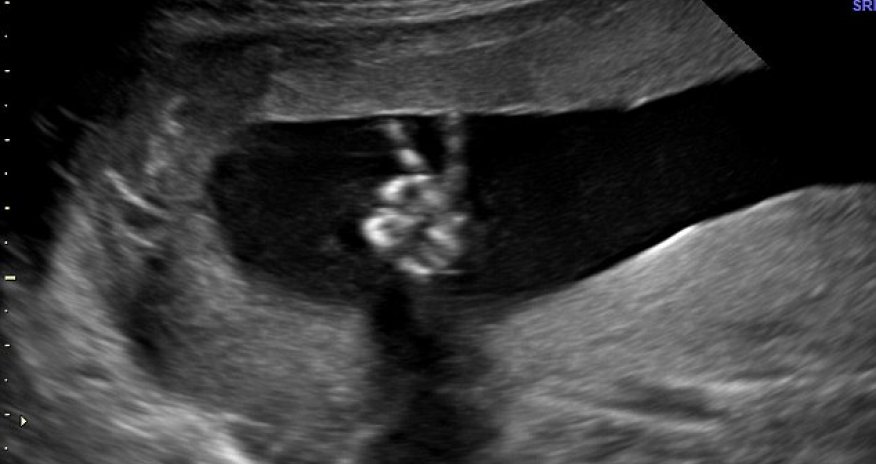

The baby pictured doing a victory V-sign in the womb

But any worries that Ed and Dee Parsons may have harboured quickly faded when they saw their baby in the womb at 20 weeks.

The child was making an unmistakable V-sign – the victory gesture associated with Winston Churchill and, latterly, with world peace.

‘The sonographer couldn't believe it – she said she had never seen anything like it before,’ said Mrs Parsons, 35.

‘It’s nice to have such an iconic image of peace when there’s so much unrest all around us. It was very reassuring.

Mrs Parsons, who has a daughter, Grace, six, from a previous marriage, said that in the 12-week scan the child had given a clear thumbs-up.